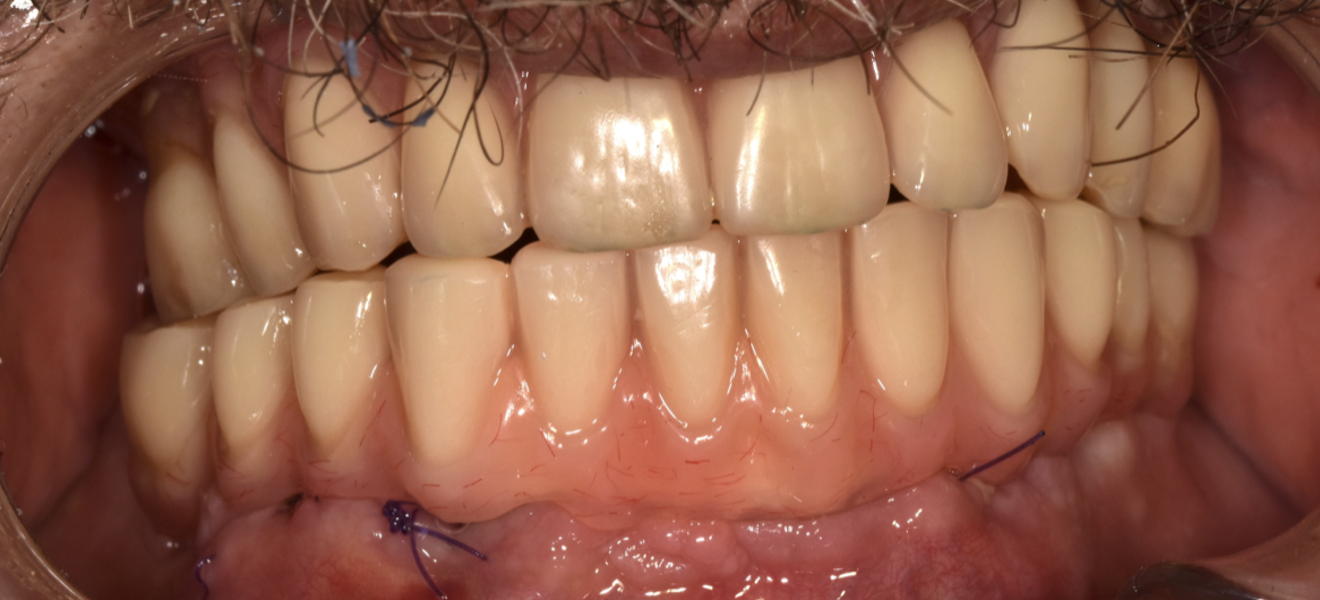

Fig. 1 : Bridges de transition CR/CO coulé/résine vissés en MCI.

Nous avons depuis la fin des années 1980 réalisé des prothèses avec succès en mise en fonction immediate après extractions et implantations. Celles-ci consistaient en une armature en CrCo coulée, sur laquelle étaient montées des dents du commerce, polymérisée en moufle de laboratoire. La rigidité de la contention était donc assurée, et la passivité de la structure obtenue par le collage de cylindres en titane dans l’armature, compensant ainsi les menues imperfections combines de l’empreinte, de la coulée du plâtre et de celle du métal (Fig. 1).

Le Zantex présente donc d’excellentes propriétés de résistance à la traction, de flexion et de compression, tout en ayant une faible densité, pour le confort du patient. Il est biocompatible, facilement réglable, et ne nécessite aucune cuisson, tout en fournissant un haut niveau de liberté de conception et de fabrication. Sa particularité est l’adhésion parfait et durable avec les matériaux utilisés en restauration dentaire. Pour la mise en oeuvre de nos MCI, le Zantex est usiné en armature sur laquelle sont monté des dents du commerce et acrylique, polymérisée en moufle de laboratoire. La rigidité de la contention est donc assurée, et la passivité de la structure obtenue par le collage de cylindres en titane à l’intrados de l’armature (Figs. 4–7).

Ces nouveaux matériaux utilisés avec toute satisfaction depuis peu nécessitent de faire face au facteur temps. C’est la raison pour laquelle tous nos travaux sont réalisés avec l’accord de nos patients, ils peuvent grâce au flux numérique être remplacés à tout moment par un nouveau bridge en cas de défaillance.